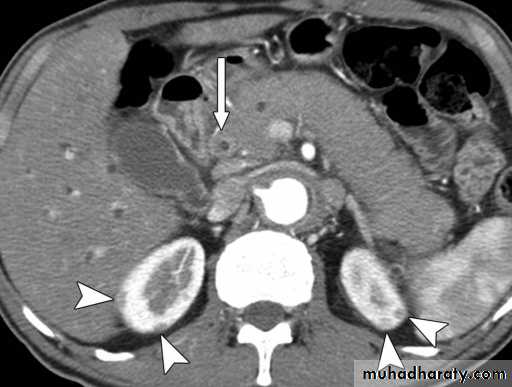

Hydatid cystAppear as large oval hypo dense area density of fluid with well defined margin , sometime at their periphery multiple flecks of calcification are seen at their periphery .

Hydatid cyst with daughter cyst , appear as multiple hypo densities rounded area within the main loculi with multiple rim of

calcification

Hydatid cyst within the liver